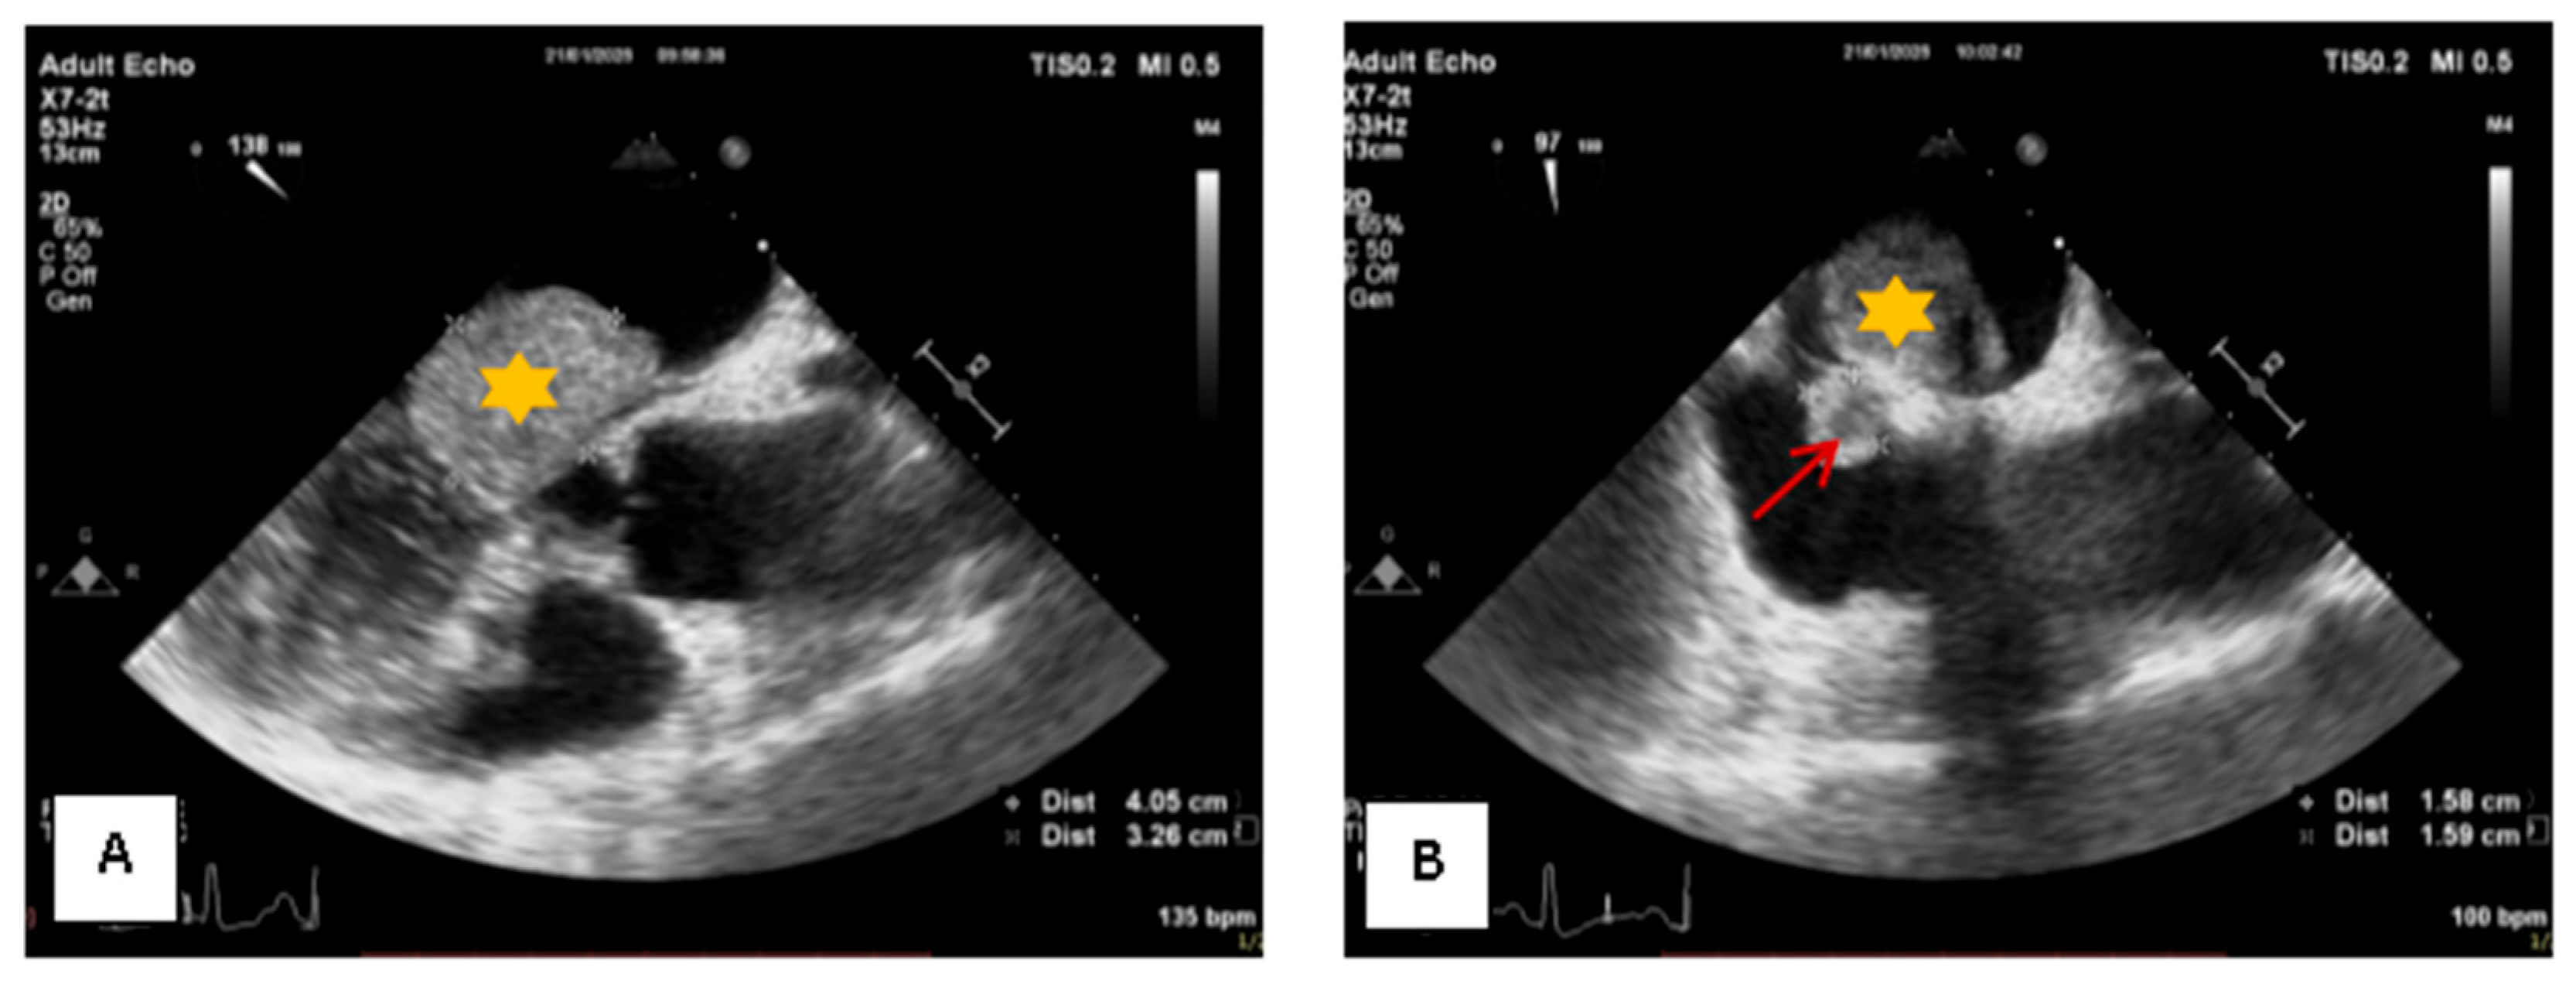

2. Case Presentation